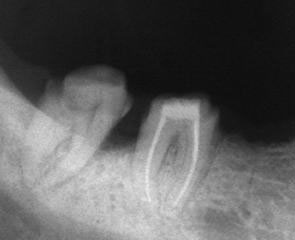

При наличие на огнище на възпаление около корените на зъба добре проведеното лечение води до изчезване на изменението. На снимката долу едва една седмица след пролекуване на каналите се наблюдава известна редукция на патологичния процес. За период от 6 месеца до 2 години е възможно да се наблюдава пълен оздравителен процес.